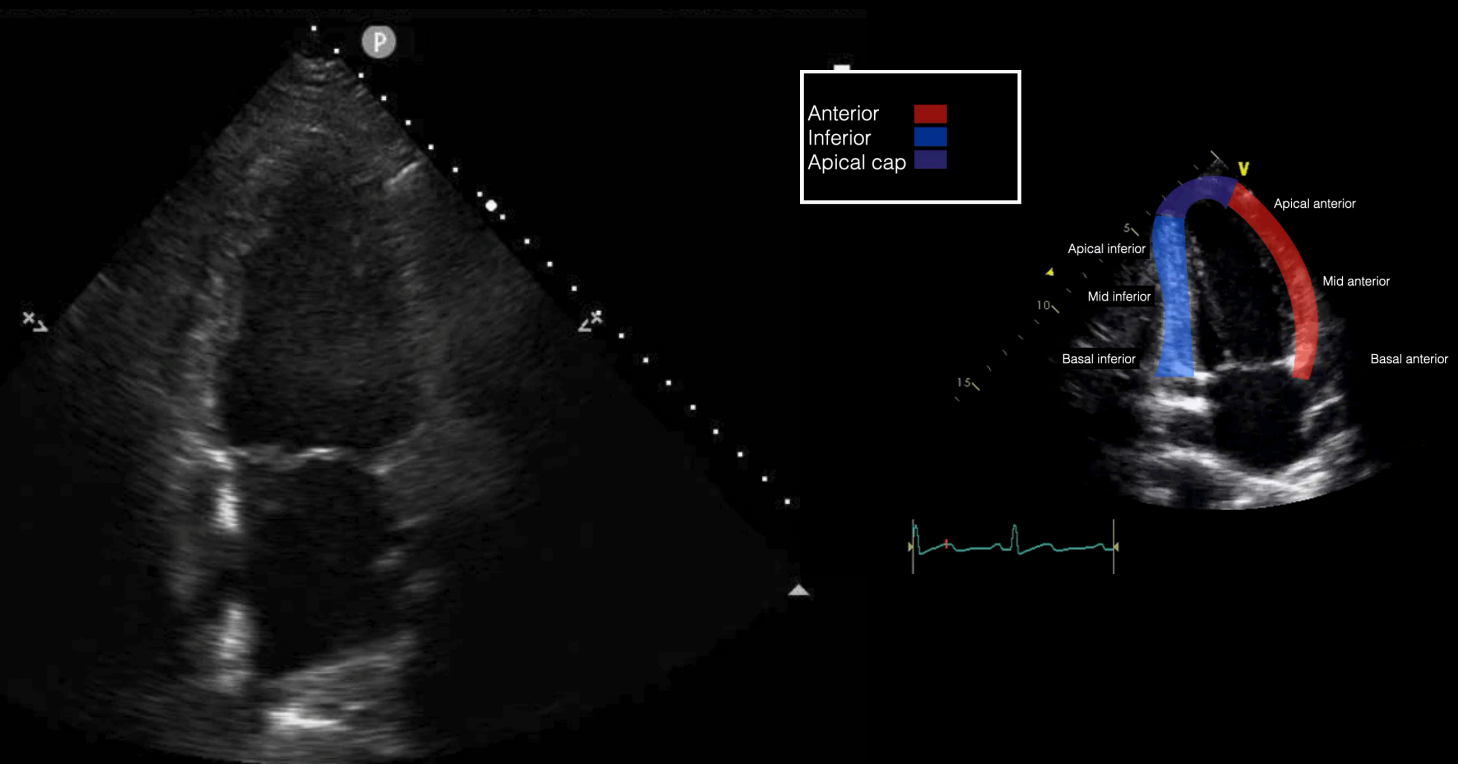

Emergency physicians should develop competency in the interrogation above segments using the parasternal long axis (PLAX), short axis (PSSX), and apical (four-chamber and two-chamber) views. We will be following cardiology convention with respect to screen orientation. PLAX can be obtained at the left 4th-5th parasternal space, with the probe marker towards the R shoulder. Rotating the probe 90º obtains the PSSX. The apical four chamber view is obtained at the point of maximal impulse, with the marker towards the patient’s left side. Rotating the probe 60º generates the apical two chamber view as demonstrated in Figure 1. This view is seldom used in EM practice but does allow for an alternate view of the anterior and inferior left ventricular walls.

Figure 1 - Apical 2-chamber view and corresponding anatomy

Apical Two Chamber (A2C)

Rotation of A4C 60º

Inferior and anterior LV